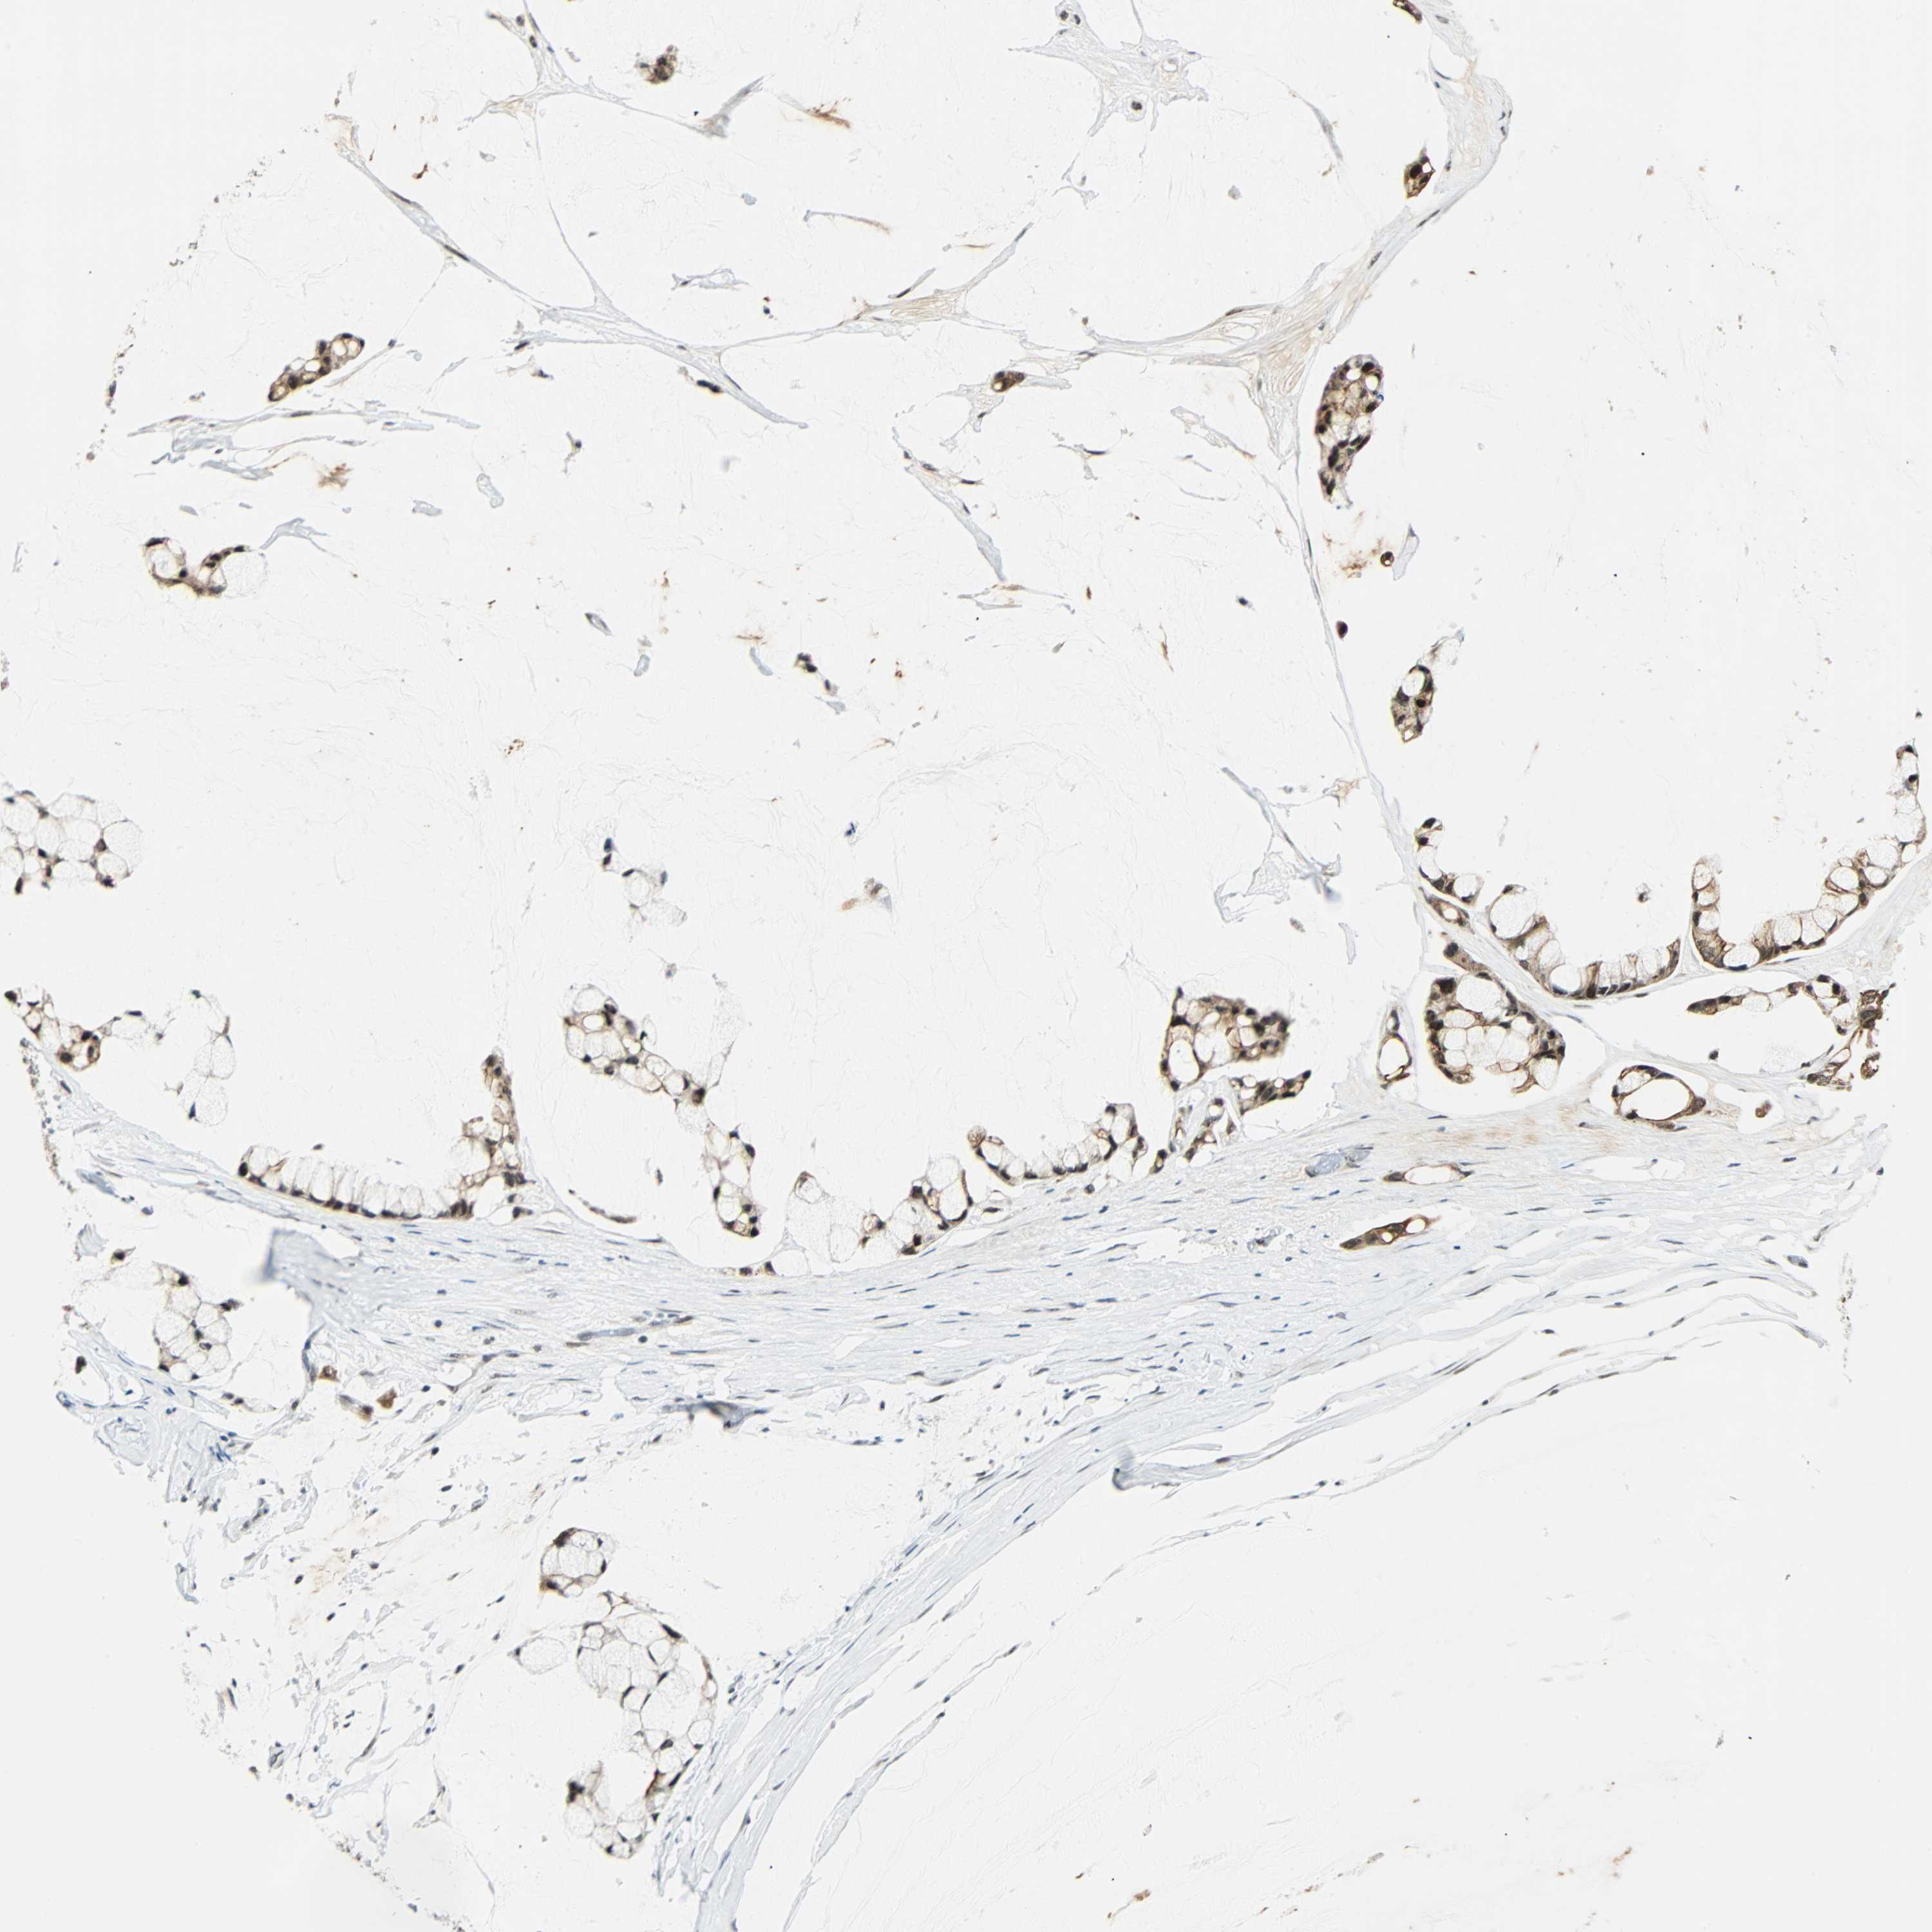

OVARIAN CANCER - Protein expressioni

A mouse-over function shows sample information and annotation data. Click on an image to view it in a full screen mode. Samples can be filtered based on level of antibody staining by selecting one or several of the following categories: high, medium, low and not detected. The assay and annotation is described here.

Note that samples used for immunohistochemistry by the Human Protein Atlas do not correspond to samples in the TCGA dataset.

Antibody stainingi

Antibody staining in the annotated cell types in the current human tissue is reported as not detected, low, medium, or high, based on conventional immunohistochemistry profiling in selected tissues. This score is based on the combination of the staining intensity and fraction of stained cells.

Each image is clickable and will lead to virtual microscopy that enables deeper exploration of all samples and also displays staining intensity scores, fraction scores and subcellular localization as well as patient and tissue information for each sample.

Antibody HPA007187

Staining

High

Medium

Low

Not detected

Intensity

Strong

Moderate

Weak

Negative

Quantity

>75%

75%-25%

<25%

None

Location

Nuclear

Cytoplasmic/membranous

Cytoplasmic/membranous,nuclear

Cystadenocarcinoma, serous, NOS

Carcinoma, endometroid

Cystadenocarcinoma, mucinous, NOS

Carcinoma, NOS